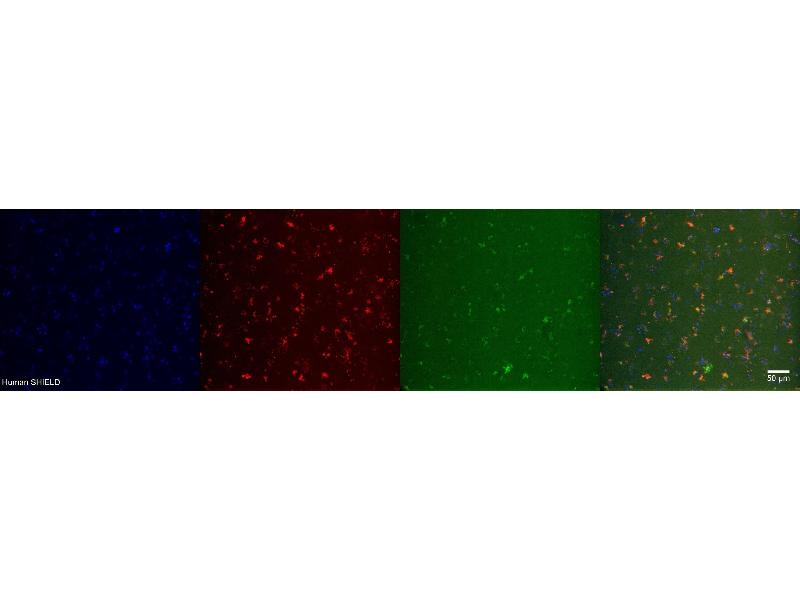

Choline Acetyltransferase Antikörper

Der Maus Monoklonal anti-Choline Acetyltransferase Antikörper wird verwendet zum Nachweis von Choline Acetyltransferase in Proben von Human. Er wurde validiert für IHC.

Immunohistochemistry (IHC)